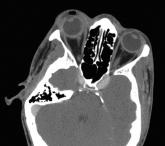

Article Liver Abscess and Metastatic EndophthalmitisAuthor:Aman D. Sabharwal, MDPublish date: December 14, 2007Read More